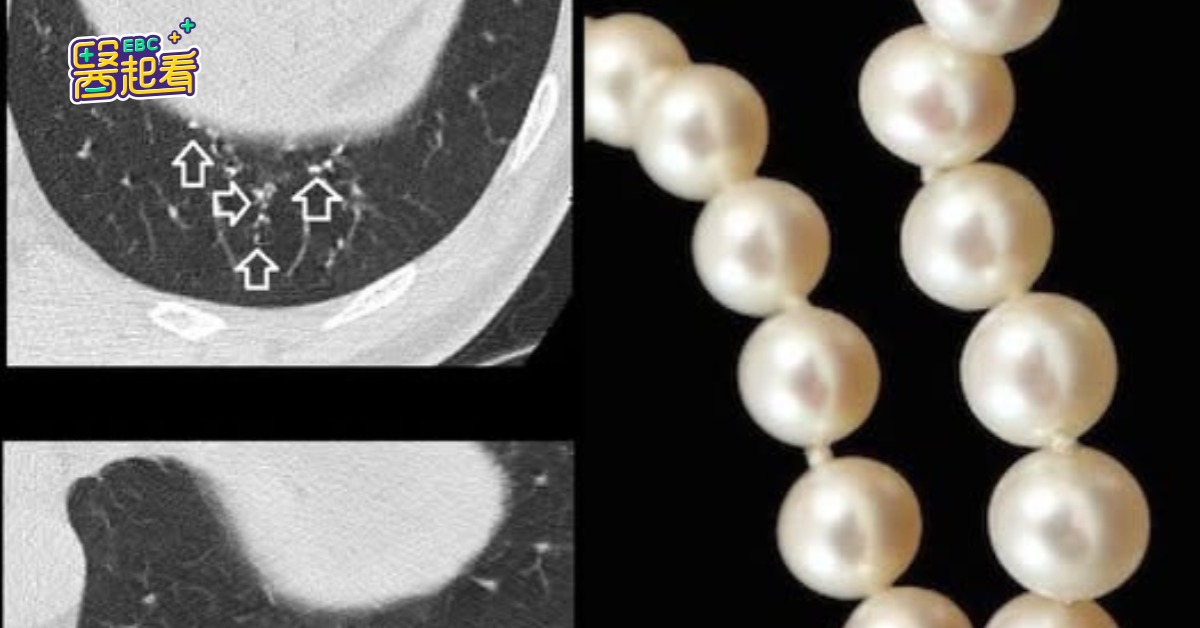

醫師在患者肺部發現20至30顆結節。(圖/翻攝自臉書@蘇一峰)

一名60歲男性患者日前接受電腦斷層檢查,醫師意外在其肺部發現多達20至30顆結節,影像呈現密集排列、宛如「珍珠項鍊」。對此,胸腔科醫師蘇一峰在臉書分享案例,並強調這種情形多屬常見,無須過度憂慮。

蘇一峰說明,患者在檢查時因看到肺部布滿亮白結節,一度擔心罹患惡性腫瘤。蘇醫師則安撫表示:「安啦!不用太擔心!」並指出這類亮白的結節通常屬於鈣化肺結節,多半是過去感染肺結核或某些特殊病毒後痊癒,所留下的肺部疤痕。

蘇一峰進一步解釋,這些結節沿著細支氣管分布,因此在影像上看起來像一串串珍珠,絕大多數都是良性結節,對健康沒有威脅,「所以很安全!」最後,他也提醒,若影像顯示為鈣化良性結節,民眾不需過度擔心,但如有其他異常症狀,仍建議依醫囑定期追蹤檢查,維護健康。